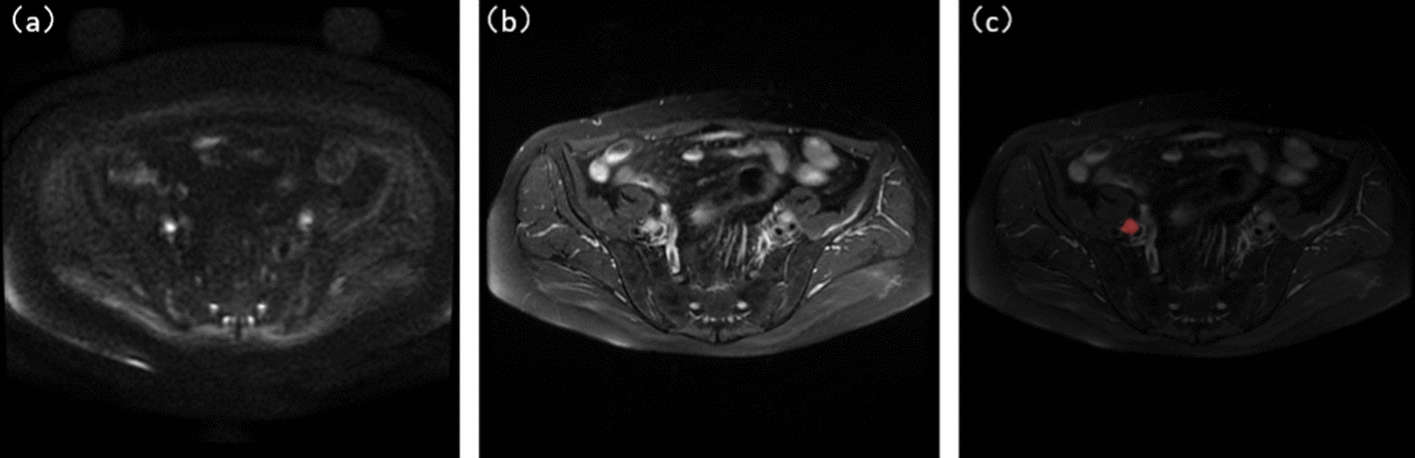

Objectives: In medical images, lymph nodes (LNs) have fuzzy boundaries, diverse shapes and sizes, and structures similar to surrounding tissues. To automatically segment uterine LNs from sagittal magnetic resonance (MRI) scans, we combined T2-weighted imaging (T2WI) and diffusion-weighted imaging (DWI) images and tested the final results in our proposed model.

Methods: This study used a data set of 158 MRI images of patients with FIGO staged LN confirmed by pathology. To improve the robustness of the model, data augmentation was applied to expand the data set. The training data was manually annotated by two experienced radiologists. The DWI and T2 images were fused and inputted into U-Net. The efficient channel attention (ECA) module was added to U-Net. A residual network was added to the encoding-decoding stage, named Efficient residual U-Net (ERU-Net), to obtain the final segmentation results and calculate the mean intersection-over-union (mIoU).